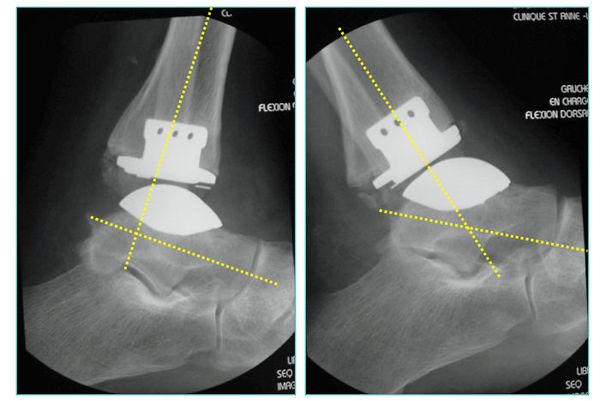

Die rekonstruktive Versorgung mit einer Sprunggelenksendoprothese ermöglicht dem Patienten im Vergleich zur Fusion eine wesentlich schnellere Mobilisierung mit Erhalt der Abrollvorgänge. 6 Wochen nach dem operativen Eingriff ist in der Regel das Laufen ohne Gips mit voller Belastung erlaubt. Dennoch eignet sich nicht jedes Gelenk für eine Endoprothese. In Fällen von hochgradigen Bandinstabilitäten oder erheblichen Knochenverformungen ist weiterhin die Fusion die Therapie der Wahl.

Abb.6: Zementfreie Dreikomponenten Sprunggelenkendoprothese. Bewegungsumfang nach Einbau der Endoprothese, gemessen im Röntgenbild

Das von uns verwendete Implantat ist charakterisiert als zementfreie, duale Titan-Hydroxylapatit beschichtete, nach dem mobile-bearing Prinzip konzipierte, totale Endoprothese des oberen Sprunggelenkes, bestehend aus drei Komponenten mit anatomischen Design.